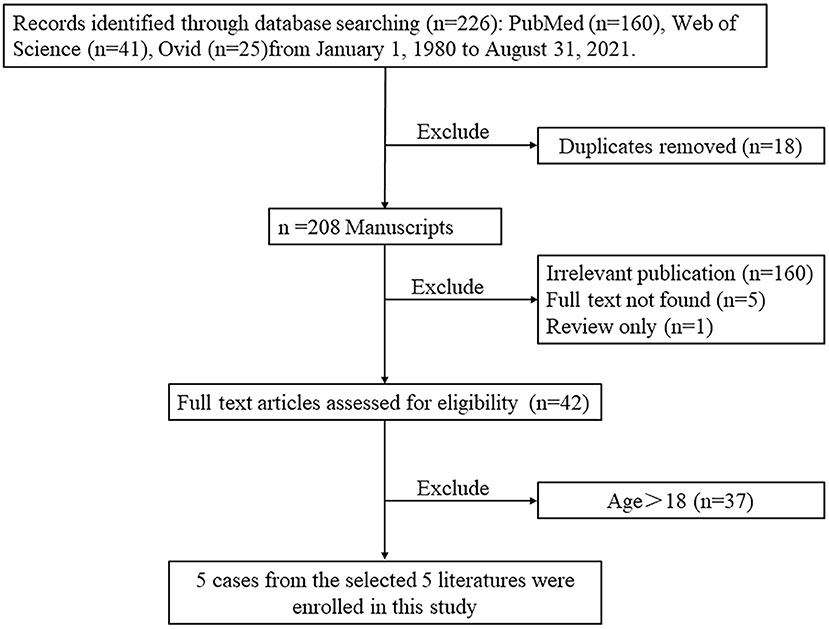

In order to present the literature review, case reports of all biatrial myxoma among child and adolescent patients in the English language were searched from the PubMed, Web of Science, and Ovid databases, dating between January 1, 1980 and August 31, 2021. Key words were used for the search, which included “biatrial myxoma,” “bilateral atrial myxoma,” “bilateral Atrial myxomas,” “pulmonary embolism,” and “cerebral embolism.” The flow chart of the literature screening process is presented in Figure 5. A total of five articles involving five cases were included in the analysis. For each case, we documented the first author, publication year, and the patient's age, sex, presentation, tumor size, image features, operation, outcome, and follow-up results (Table 1).

Figure 5. The flow chart of the literature screening process for biatrial myxoma in children and adolescent patients.

According to the literature, from January 1980 to August 2021, only 44 cases of biatrial myxoma have been reported. Our results revealed a predominance of biatrial myxoma between 40 and 65 years of age (52.2% of the cases), however, only six cases have been reported for patients of 18 years or less (about 13.6%; including of our case) of biatrial myxoma, comprising three girls and three boys, with a female to male ratio of 1:1. Remarkably, the presentation of these patients was predominantly associated with embolic events, such as pulmonary embolism and cerebral embolism. However, all patients with pulmonary and cerebral embolism had only one or the other, and the occurrence of both pulmonary and cerebral embolism simultaneously has not been reported. Fortunately, most patients were discharged after surgical operations, suggesting that biatrial myxoma has a relatively good prognosis.